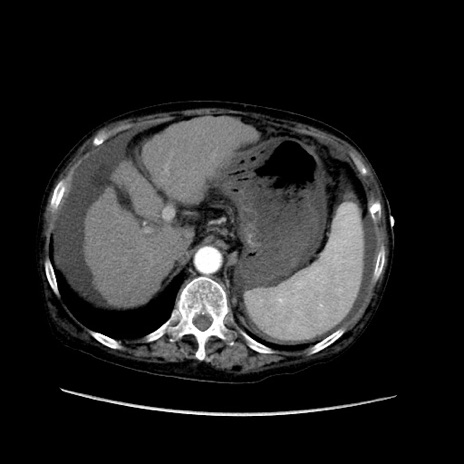

症例31(横断像)

【症例】80歳代 女性

【主訴】腹部膨満感

【現病歴】他院にて肝硬変にてフォロー中。1週間前から便秘、腹部膨満感、臍部腫瘤あり受診となる。

【既往歴】肝硬変

【身体所見】腹部膨隆あり、皮膚変化なし、疼痛なし。